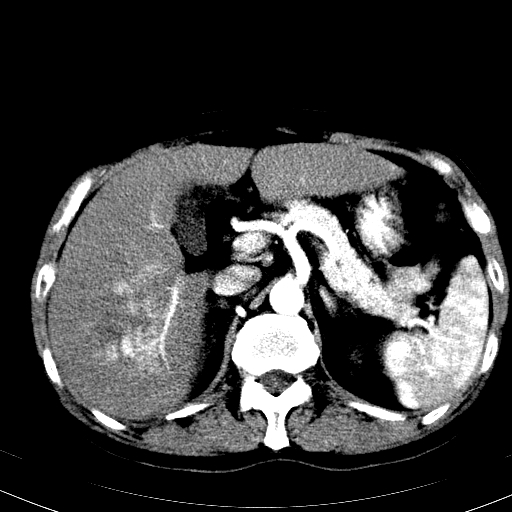

以下是引用卜一在2008-6-23 15:38:00的发言:[br]本例延时期的图象未扫完,单纯平扫 动脉期及门脉期特征分析:平扫低密度较大肿块,内见不规则出血灶,界限清楚。动脉期边缘结节样强化,门脉期病灶边缘进一步强化并范围明显缩小。因此考虑:血管瘤伴出血!

以下是引用深泽交通医院在2008-6-23 16:40:00的发言:[br]考虑肝癌伴出血.诊断依据:平扫瘤壁结节密度低于肝实质,动脉期壁结节明显强化,门脉期略低于肝实质密度[br]病灶有明显的假包膜,

以下是引用qiuleiyu在2008-6-23 20:53:00的发言:[br]支持;血管瘤伴出血可能大.